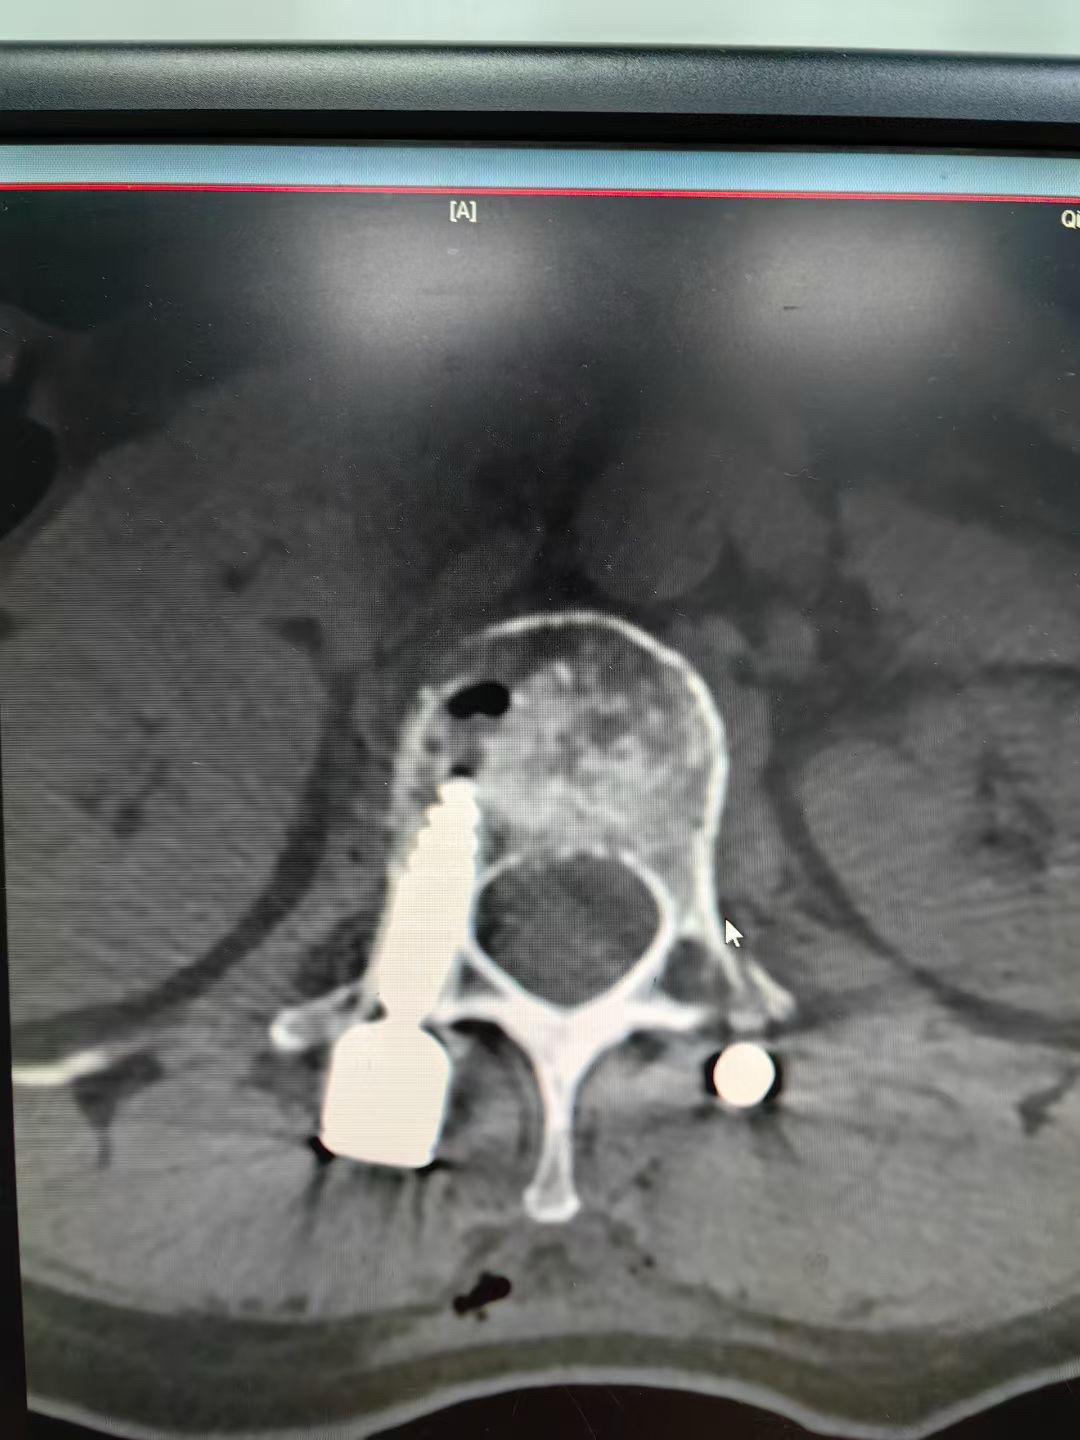

腰1爆裂性骨折,通过闭合复位也是能达到理想的

62岁外伤导致腰3爆裂性骨折,闭合复位,椎体复位稍差,但是椎管的复位还是满意